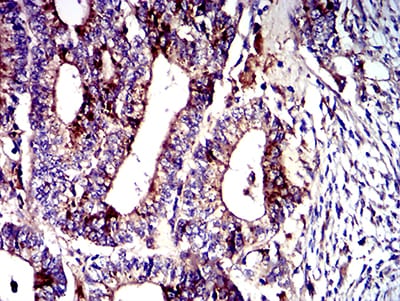

TD-313773.jpg

Immunohistochemical analysis of paraffin-embedded human lung cancer tissues using CD107b mouse mAb with DAB staining.

TD-313774.jpg

Immunohistochemical analysis of paraffin-embedded human cervical cancer tissues using CD107b mouse mAb with DAB staining.